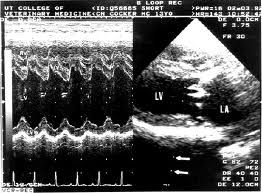

در اکوی دو بعدی تصویر دقیقی از آناتومی قلب ایجاد میشود و در این نوع اکوکاریوگرافی بیشتر برای اندازهگیری اندازه قلب و اجزا و میزان کارایی آنها مورد استفاده قرار میگیرند. از سوی دیگر قدرت عضلانی قلب و بویژه توانایی بطن چپ در بیرون راندن خون از قلب توسط اکوی قلبی قابل ارزیابی میباشد.